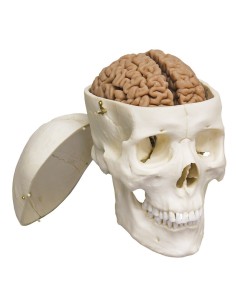

Dal cranio in 22 parti con incastri magnetici ai modelli di colonna vertebrale, da quelli di articolazioni a quelli di cuore, ogni pezzo della nostra collezione è progettato per un’immersione totale nello studio dell’anatomia umana. I nostri modelli, realizzati tramite scansioni di ossa vere, garantiscono un’esperienza tattile autentica e una fedeltà di peso quasi identica agli originali.

Essenziali per studenti e professionisti, i nostri modelli anatomici sono strumenti didattici che permettono di osservare le strutture anatomiche con precisione, eliminando la necessità di dissezioni o studi invasivi. Sono inoltre utili per spiegare ai pazienti le patologie, rendendo la comunicazione più efficace e risparmiando tempo prezioso.